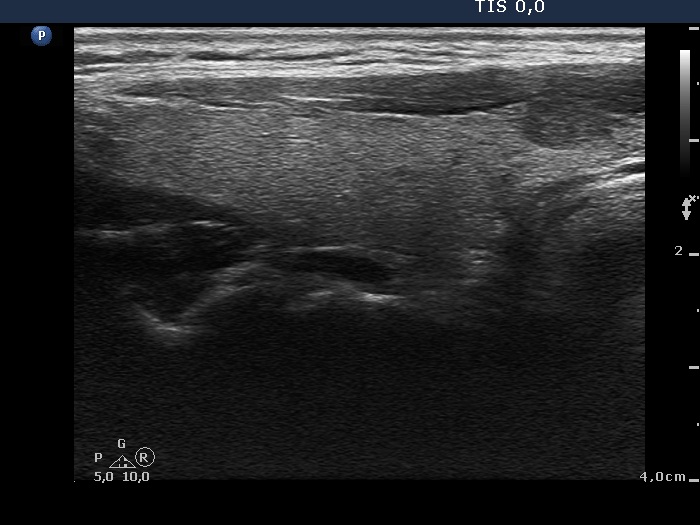

Longitudinal scan |

The nodule is brighter than the strap muscle while darker than the extranodular tissue and does not show any suspicious sign. This is an EU-TIRADS 4 lesion.